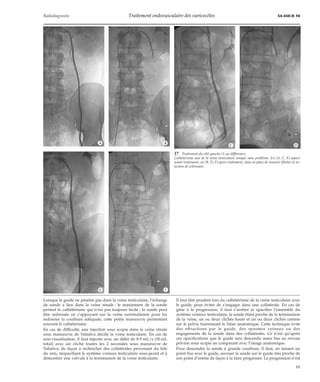

16 Traitement du côté droit (deux cas différents).

A, D. Opacification.

B, E. Mise en place d’un microcathéter (1), dont l’extré-mité

(flèche) est en regard de l’épine sciatique.

C, F. Contrôle en fin de traitement : thrombose du sys-tème

veineux testiculaire au niveau lombaire.

17 Traitement du côté gauche (3 cas différents).

Cathétérisme aisé de la veine testiculaire unique sans problème. En (A, C, E) aspect

avant traitement, en (B, D, F) après traitement, mise en place de ressorts (flèche) et in-jection

de sclérosant.